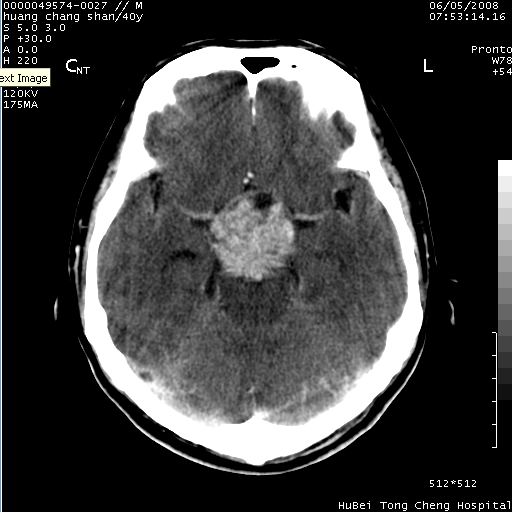

患者 m,40y。头痛,视力模糊,多饮多尿,性欲减退半年余。

行ct平扫+增强,图象如下:

肿瘤强化明显、鞍部骨质结构未见增大、破坏,考虑脑膜瘤可能性大

鞍背无破坏和明显受压,病变明显均匀强化,边界清晰。鞍上区脑膜瘤可能性大,不除外生殖细胞瘤。

平扫病灶呈等密度,增强后强化明显,均匀一致,结合病史首先考虑:垂体瘤。脑膜瘤不支持,因为脑膜瘤平扫多为实性呈均匀高密度影像,内分泌症状多不明显,垂体内分泌素测定正常。

鞍上池肿瘤,鞍背及垂体窝形态变化不明显,病灶强化密度均匀且高度强化,考虑实性颅咽管瘤、生殖细胞瘤及脑膜瘤可能。

结合临床考虑鞍上生殖细胞瘤可能性大于脑膜瘤(增强未见脑膜围征),建议结合冠状位扫描看病灶起源及垂体窝、鞍底情况。垂体窝内未见明显软组织密度影,垂体窝未见扩大,暂不考虑垂体瘤;病灶较大,未见囊变及钙化,颅咽管瘤不支持。期待结果!

1、头痛,视力模糊,多饮多尿,性欲减退半年余,提示:肿瘤为功能性肿瘤。

2、ct表现:肿瘤呈类圆形,均匀略高密度,无囊变,无钙化。侧脑室有扩大。

3、首先考虑:功能性垂体大腺瘤。

4、鉴别诊断:脑膜瘤,瘤体内点状钙化最具特征性,常位于鞍结节。颅咽管瘤,蛋壳样钙化,常有囊变。动脉瘤,位于鞍旁,强化与动脉一致。有时尚需与发生于鞍区的生殖细胞瘤鉴别,生殖细胞瘤钙化亦较常见。

5、友情提示:下回发现鞍区占位性病变,最好加扫冠状位,了解肿瘤与蝶鞍的关系及蝶鞍骨质的改变。